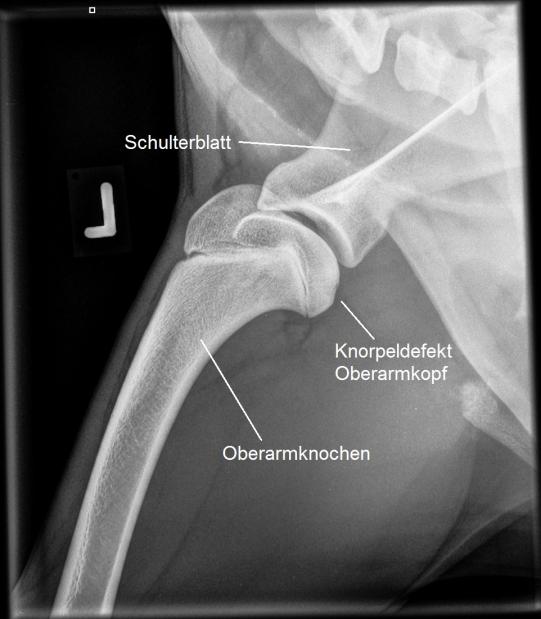

Die Ellbögen erscheinen verhältnismässig unauffällig, allerdings sind fragliche Veränderungen an einem kleinen Gelenksfortsatz (Processus Coronoideus) nicht ganz ausgeschlossen. In den Schultergelenken werden wir jedoch eindeutig fündig: Beide Gelenke zeigen im Bereich des Oberarmkopfes eine Schädigung des Gelenkknorpels an der typischen Stelle im hinteren Teil des Gelenkes: Inox leidet an einer sogenannten Schulter-OCD (Osteochondrosis Dissecans).

Bei diesem wachsenden Sporthund ist es wichtig, dass das Problem baldestmöglich aggressiv angegangen wird. Inox wird an die Orthopädieabteilung des Tierspitals Bern überwiesen, wo mittels Gelenksspiegelung die Diagnose bestätigt und das Problem operativ angegangen wird: Mit den ins Gelenk vorgeführten Instrumenten werden die losen Knorpelteile entfernt und der unterliegende, freiliegende Knochen debridiert (d.h. von losem Gewebe befreit). In der Folge wird der Knorpeldefekt im Zuge der Heilung durch Faserknorpel ersetzt.